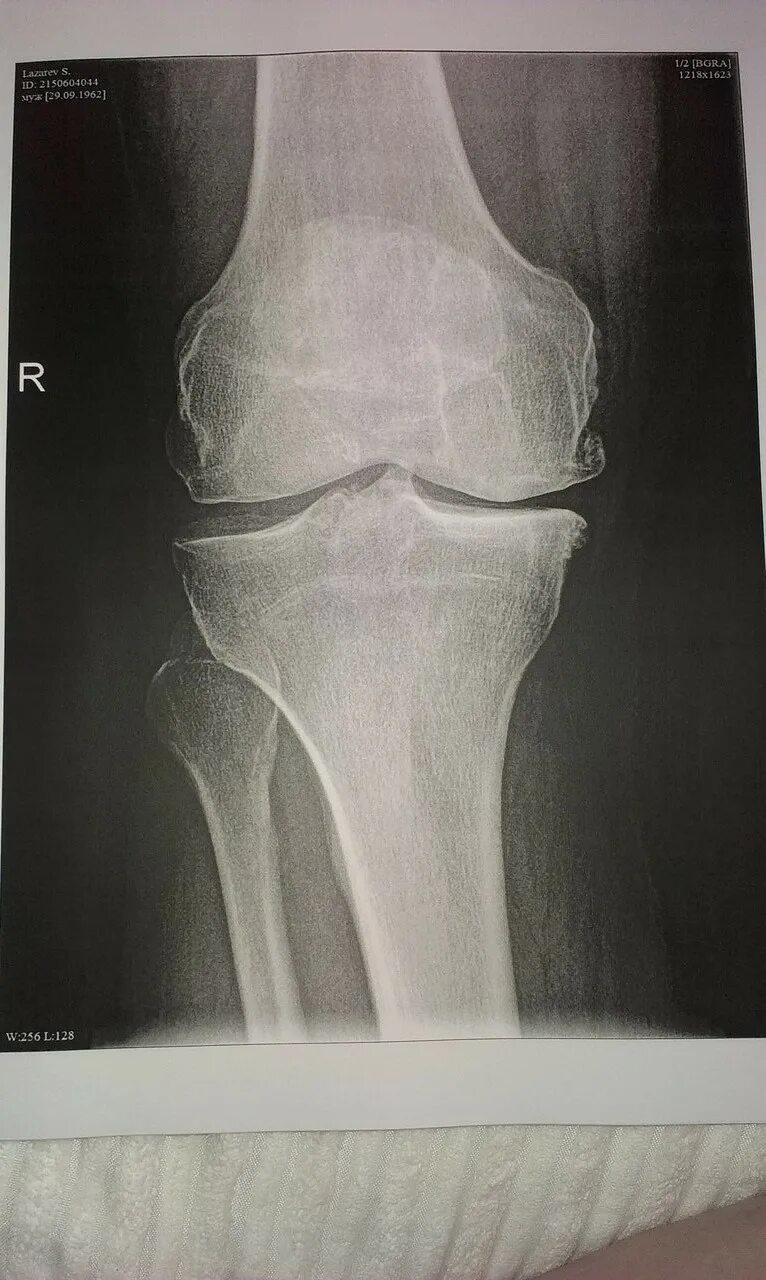

Артроз коленных суставов 2 степени инвалидность